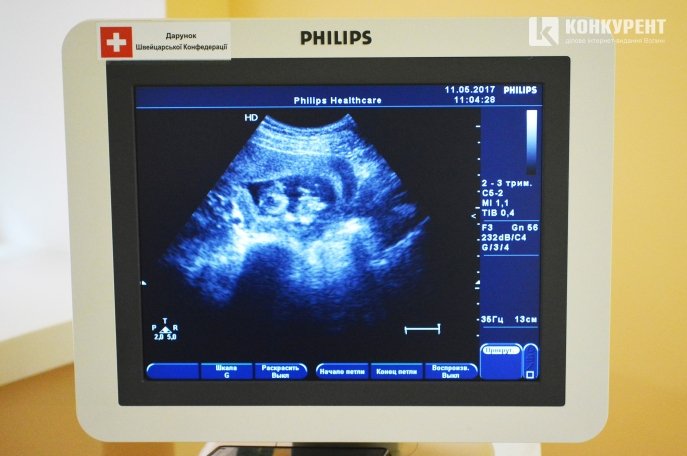

Це відділення ультразвукової діагностики, де виконуються обстеження вагітних жінок та плоду. Перед тим, як проходити тут діагностику, майбутні мами стають на облік (бажано до 12 тижня вагітності, щоб був час на здачу аналізів та УЗД).

«За період вагітності у жінок є три-чотири планових обстеження: два обов'язково, а інші за показами. Першу УЗД-діагностику бажано робити на 11-13 тижні вагітності, а другу – на 19-20 тижні. На цих УЗД ми шукаємо вади розвитку дитини. Якщо вади розвитку плоду несумісні з життям, то ми рекомендуємо вагітність перервати. У таких випадках розповідаємо все: що ми виявили та що чекає на дитинку у разі її народження. Жінки самі приймають рішення щодо того, виношувати їм чи перервати вагітність», – розповів лікар ультразвукової діагностики Юрій Шворак.